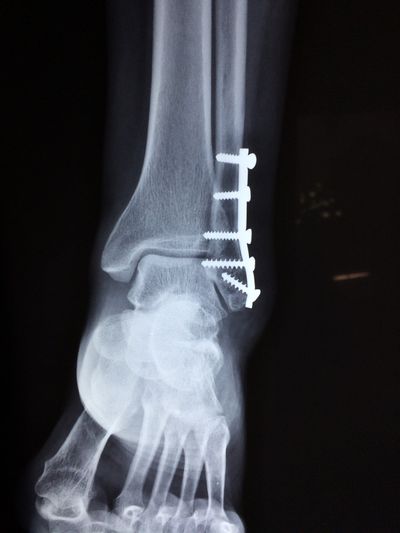

Clinical metagenomic sequencing for species identification and antimicrobial resistance prediction in orthopaedic device infection